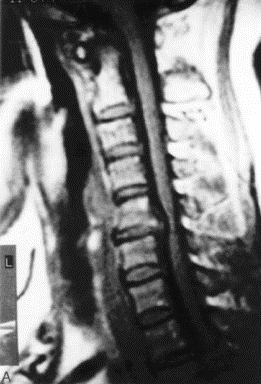

MRI成像显示颈椎椎间盘、椎体、韧带及脊髓,根据信号改变作出判断

脊髓型颈椎病MRI表现